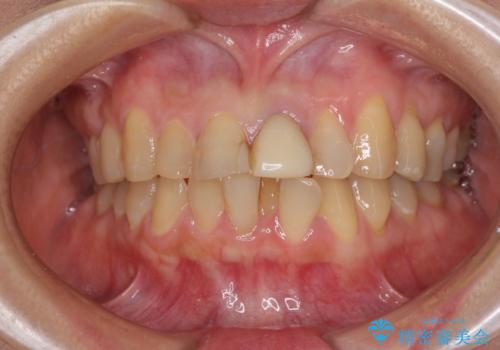

前歯のデコボコをワイヤー矯正できれいに整える

- 前歯のデコボコと変色した前歯を気にして来院された患者様です。

抜歯矯正により口元を引っ込めることも検討しましたが、特に口元の突出感は気になっていないとのことで、非抜歯にてワイヤー装置で矯正治療を行うこととしました。

気になっていた前歯の変色も、矯正治療後にオールセラミッククラウンにて補綴治療を行うこととしました。